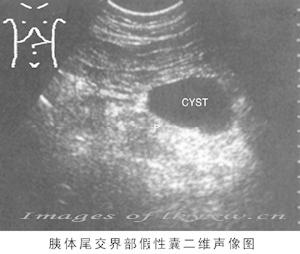

2、B超檢查 B超檢查是診斷胰假性囊腫的一項簡便而有效的手段,典型者於上腹可探及一位置明確、範圍肯定的液性暗區。B超對鑑別包塊和囊腫特別有助,對胰假性囊腫的診斷正確率可達73%~91%。動態的超聲探查可了解囊腫大小的改變。此外,在B超引導下,可作囊穿刺,抽取囊液作生化和細胞學檢查。

一般認為胰腺假性囊腫多見於胰體、尾部,但近年來由於B型超聲顯像檢查的廣泛套用,胰頭部假性囊腫的發現率明顯增加。Sugawa及WALT報告50%的假性囊腫位於胰頭部。